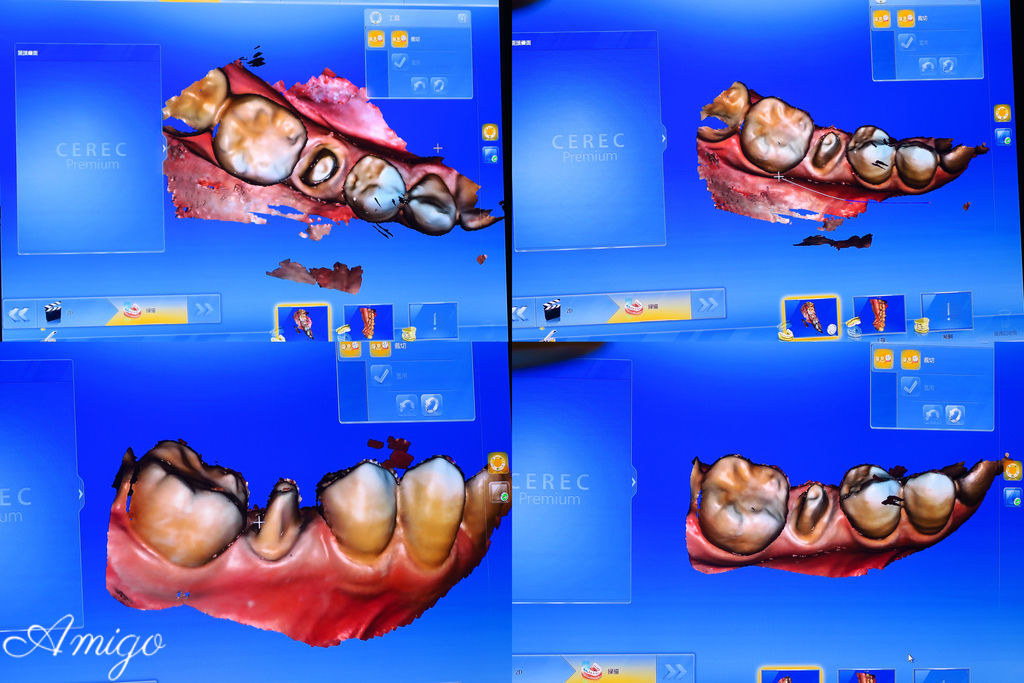

透過大螢幕來觀看患者口內狀況以及3D影象投射

整個治療過程都在螢幕上清楚呈現

當天的case是一位做全瓷冠假牙的患者

本次病患做假牙的部位是畫面左邊倒數第三顆的小臼齒

將口內牙齒狀況以3D彩色影像精準呈現在技師的工作螢幕上

技師在診間內即可使用全瓷假牙設計軟體預視患者的牙齒

由電腦運算製作假牙

只需透過電腦影像即可模擬調校出形狀大小似真牙的全瓷冠假牙

技師熟練迅速且精細地在畫面上調校曲線

為的就是待會可以磨出一顆精緻度極高的完美牙冠

電腦模疑出假牙完成的樣子

這時技師再次的進行修整

讓牙齒的弧度及咬合等方面更符合患者的使用需求